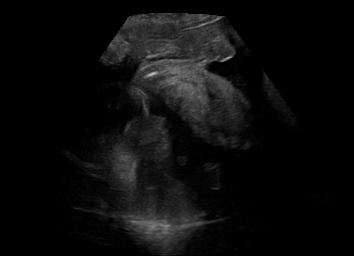

Real in-vivo images. 22 ultrasound sequences were collected using a GE Voluson E8 machine during standard fetal screening exams of 8 patients. Each sequence is several seconds long. We extracted all 4427 frames and resize them to , see Fig. 2 for some examples. The resulting image set was randomly split into training-validation-test sets by a 80-10-10% ratio.